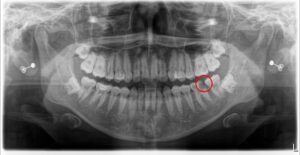

まずは、論より証拠。こちらのレントゲン画像をご覧ください。

■ わずか2年で、ここまで悪化してしまう現実

これは、ある患者様の2年前(16歳時)と現在(18歳時)のお口全体のレントゲン写真です。 一見すると分かりにくいかもしれませんが、実はこの2年間で、私たち歯科医師が「これはまずい…」と危機感を覚えるほどの変化が起きています。

さらに、特に進行が目立つ部分を拡大して撮影したものがこちらです。

いかがでしょうか。 歯の内部に、黒く大きな空洞(透過像)が広がっているのがお分かりいただけるでしょうか? 2年前には影も形もなかった虫歯が、わずか2年で神経の近くまで破壊を進めてしまっているのです。